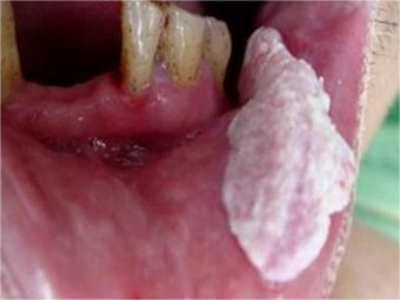

口腔

口腔白斑病口腔黏膜疣形白斑图

口腔白斑病表现为黏膜疣形白斑,表面稍粗糙,界限清楚,突出口腔黏膜的表面,质地较硬,不易推动,咀嚼时容易反复造成外伤,从而引发溃疡。